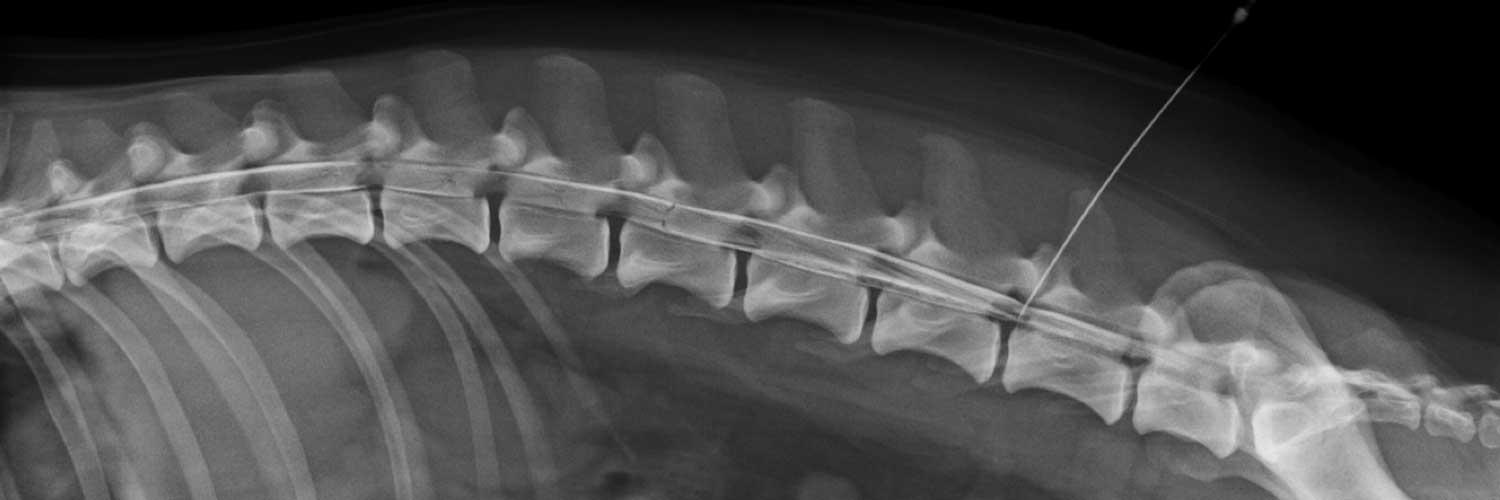

• Pruebas avanzadas de imagen

• Procedimientos quirúrgicos: patología discal, patologías congénitas, procesos traumáticos, neoplasias, ...